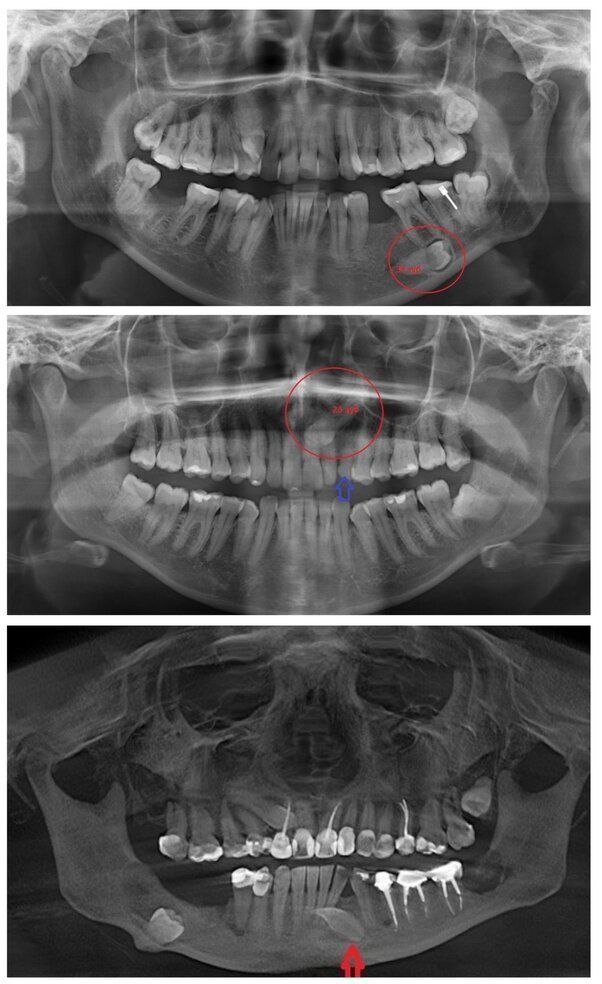

Основной метод диагностики – это плоскостной рентгеновский снимок (ОПТГ) или КТ. Иногда такой зуб можно "увидеть" на осмотре по косвенным признакам , но чаще всего они "спрятаны" в десне и обнаруживаются при проведении дополнительных методов обследования.